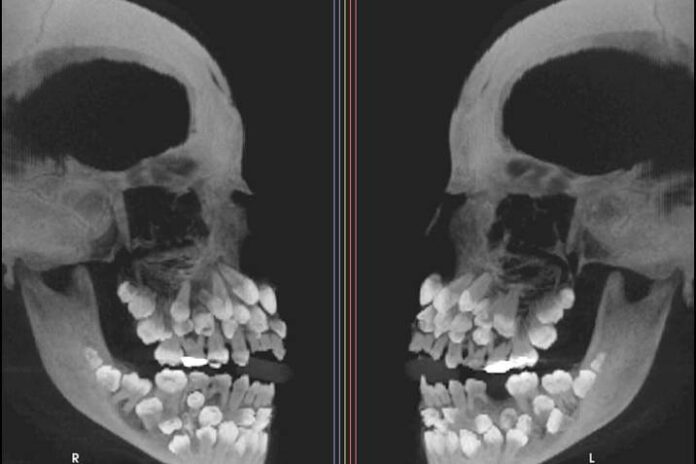

La menor padece de una anomalía llamada “hiperdoncia múltiple”, que provoca que tenga más piezas dentarias que un ser humano adulto.

Ella tenía muchas más piezas dentarias de las 32 que habitualmente tienen las personas. Luego de que se le realizara una tomografía computarizada, los especialistas descubrieron con gran asombro que la pequeña contaba nada menos que con… 81 dientes.

Los especialistas determinaron que de las 81 piezas, 18 eran dientes caducos, 32 permanentes y 31 supernumerarios o múltiples. Estos últimos representan una infrecuente anomalía del desarrollo de la cavidad bucal, pueden aparecer en cualquier zona de la arcada dentaria y afectar cualquier órgano dental, señalaron los especialistas.

Una de las imágenes que muestra el informe sobre este inusual caso es una tomografía computada de haz cónico (CBCT) tomada desde los dos laterales del rostro de la pequeña. Allí se ve, en blanco sobre negro, la exagerada cantidad de piezas dentales con las que cuenta esta paciente, que asemejan a un ramillete de dientes distribuidos tanto en el maxilar superior como en la mandíbula.